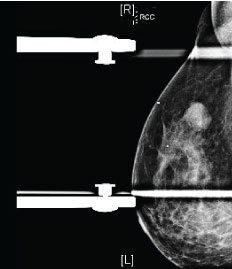

Magnetic resonance imaging (MRI) is extremely sensitive for the detection of TNBC, with the morphologic characteristics of TNBC on MRI more suspicious than those seen on mammography or ultrasound (Figure 3) [16]. In a study examining forty-four patients with TNBC, Dogan, et al. found that MRI was 100% sensitive for the detection of these tumors as compared to sensitivities of 91% and 93% for mammography and ultrasound, respectively [13]. The predominant presentation of TNBC in that study was an enhancing mass, seen in 34 patients. The most commonly reported mass shape was round or oval, described in 35% of patients, with dominant mass margins reported as irregular or spiculated in 47% and 41% of cases respectively. The most frequent contrast enhancement pattern was rim enhancement, present in 76% of cases. Enhancing internal septations were seen in 8 patients. The other 10 patients in this study showed non-mass enhancement. A study by Uematsu, et al. [17] reviewed 59 patients and demonstrated that findings of a mass lesion, rim enhancement pattern, smooth mass margins, and persistent enhancement kinetics were associated with TNBC [17]. Of these findings, Teifke, et al. [18] suggest that rim enhancement was the most accurate MR finding for determining ER status. Although there is a strong association between unifocal lesions and TNBC [17], multifocality has been reported in the literature in 21% of cases [19]. TNBC tend to be larger in size on MRI than other subtypes, with an average tumor size of 4.1 +- 2.7 cm [19]. Prominent skin enhancement was also a frequent finding in this study, suggesting invasion of the dermal lymphatics [19]. High intratumoral T2 signal intensity, which is also associated with TNBC [13,17,19-21], has been shown to be strongly associated with intratumoral necrosis [20]. Osman, et al. demonstrated a 90% correlation of high T2 signal on MRI with internal necrosis on pathologic examination [20]. This is clinically significant, as internal necrosis is related to poor clinical outcomes and aggressive tumor biology [22]. The presence of necrosis has been associated with reduced relapse free-survival as well as increased mortality in both node-positive and node-negative patients [22,23].

Figure 3: Magnetic resonance findings in triple-negative breast cancer (TNBC). Post-contrast axial and coronal T1 fat-suppressed images of the bilateral breasts demonstrate a round mass with circumscribed margins and rim enhancement in the right breast at posterior depth, representing a biopsy-proven TNBC. View Figure 3